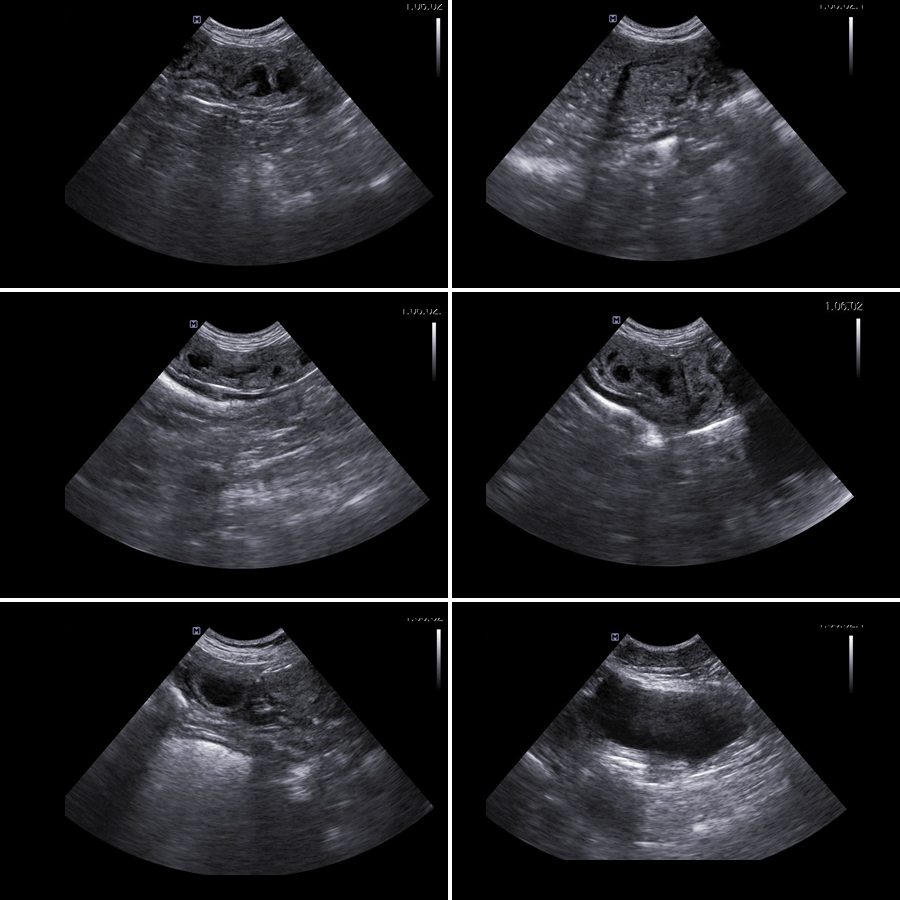

▶ 초음파 검사

영상 검사를 통해 확장된 자궁이 관찰되었고, 이것은 자궁 축농증이라고 진단되었습니다.